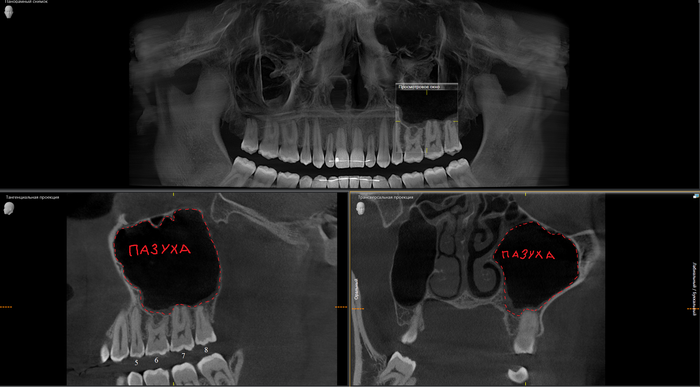

Ниже, на панорамном снимке зубов, мы наблюдаем критичную убыль костной ткани вокруг имплантатов на верхней челюсти.

Оранжевая пунктирная линия - было,

красная - стало.